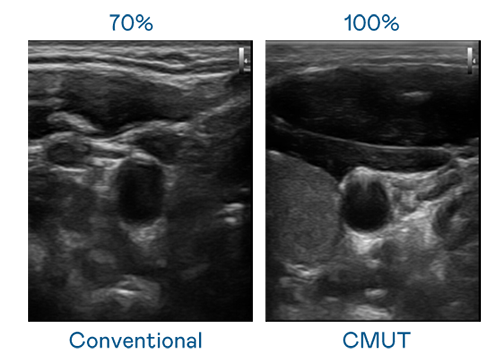

CMUT 技术是一种用电容式微机电元件来产生超音波讯号的技术。与传统 PZT 压电式技术相比,CMUT 频宽增加 30%,更宽频的超音波讯号让影像解析度大幅提升,是实现高影像品质医疗超音波扫描、促进精准医疗发展的关键技术。

超音波影像的解析度高低,首先取决于探头能发出的讯号频宽。AG电子 CMUT 可提供高清晰的超音波讯号,提供高频宽、高灵敏度、影像纹理细节更高的超音波影像,协助医护人员缩短影像判读时间及利用精准的医疗影像进行诊断。